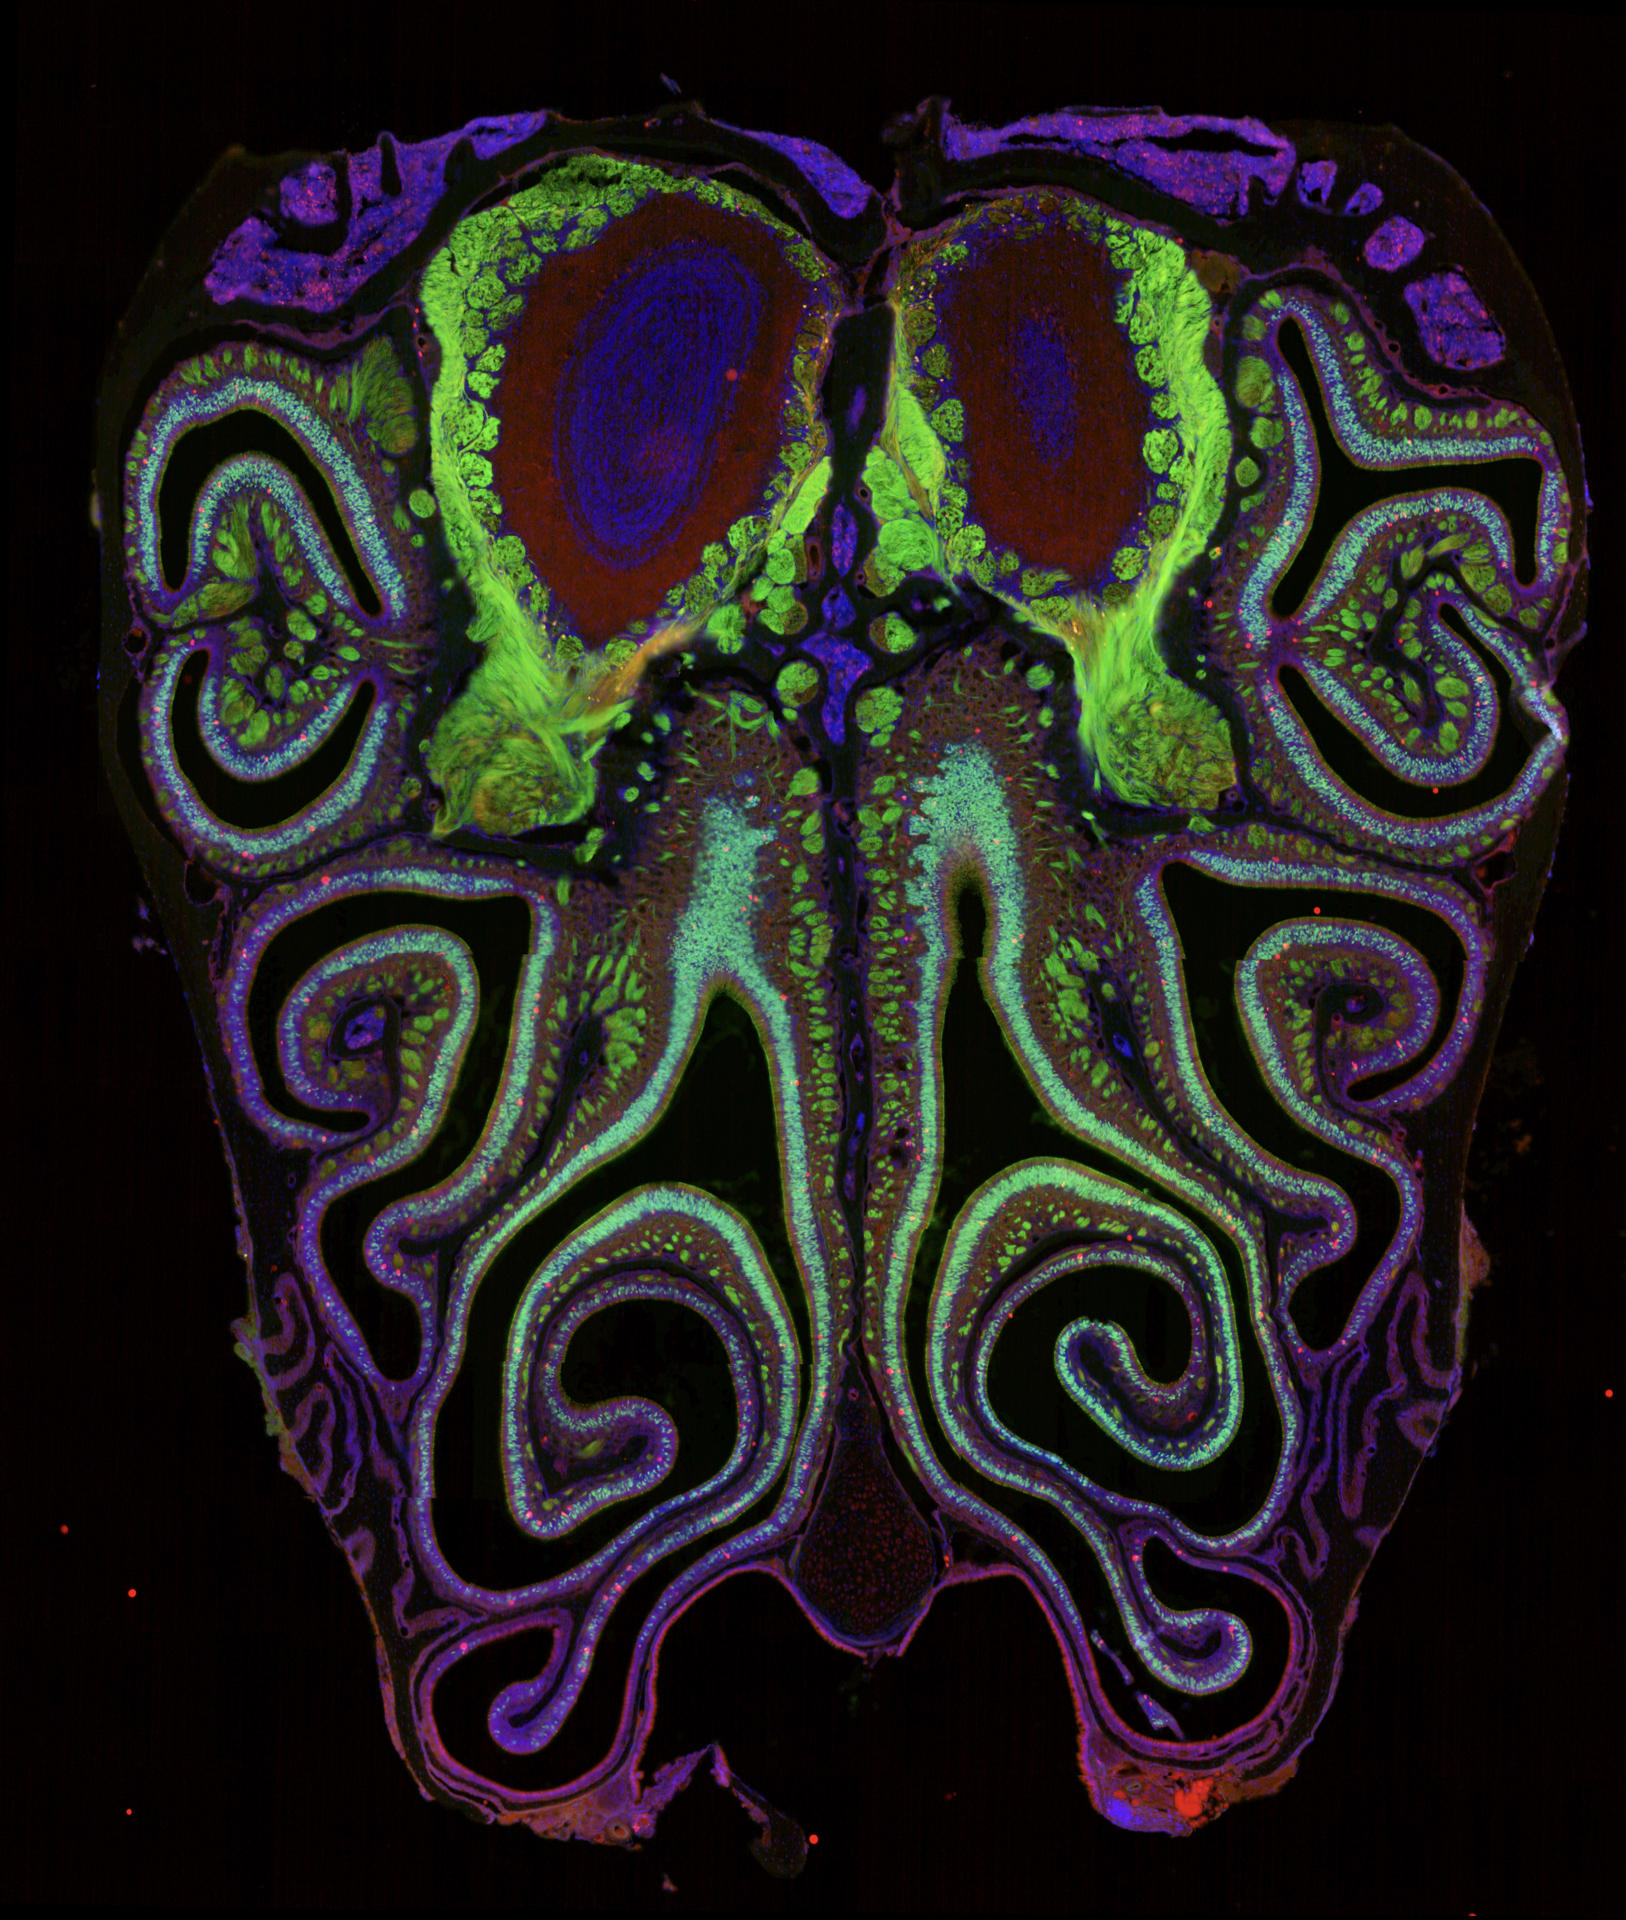

Los detalles del mapa, que revela que las neuronas que expresan estos receptores olfativos están altamente organizadas en bandas estrechas horizontales según el tipo de receptor, se han publicado este martes en Cell.

Además, el equipo descubrió que el mapa de receptores en la nariz coincide con los mapas de olor en el bulbo olfativo del cerebro, lo que proporciona pistas sobre cómo se mueve la información desde la nariz hasta el cerebro.

Así, descubrieron que las neuronas se organizan en franjas horizontales estrechas y superpuestas desde la parte superior de la nariz hasta la inferior, según el tipo de receptor de olor que expresan.

Este mapa de receptores altamente organizado fue consistente en todos los ratones y reflejó la organización de los mapas de olor en el cerebro, tal como los investigadores han observado en la visión, el oído y el tacto.